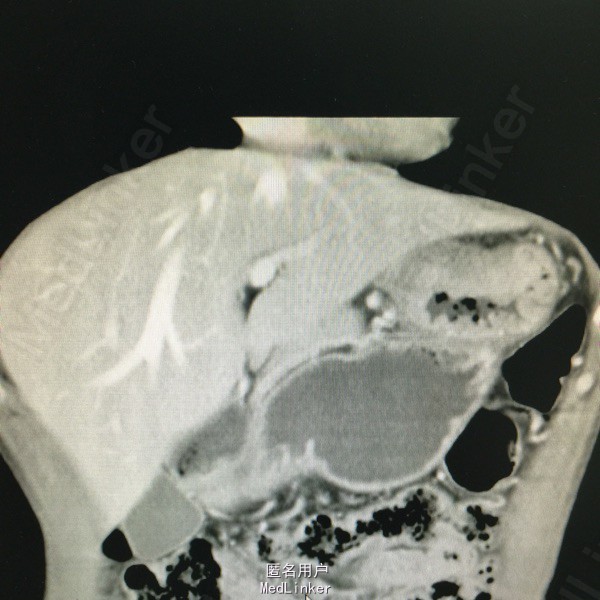

男,47岁,上腹部疼痛一年入院。检查胃镜提示胃底部恶性肿瘤。

上腹部压痛。全腹CT提示胃癌,腹腔转移。

胃癌,失去手术指证,给予2次化疗后不能耐受。改用替吉奥口服。